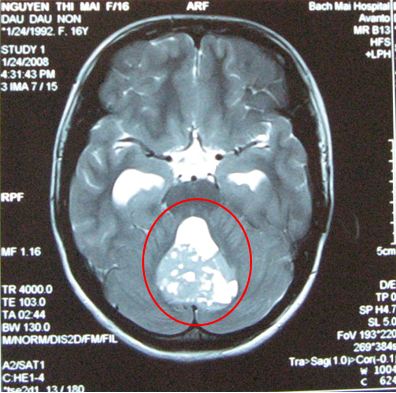

Trường hợp 1: Bệnh nhi Nguyễn Thúy H, nữ 8 tuổi vào viện vì lí do đau đầu, nôn, sụp mi mắt trái. Bệnh nhân đã được chụp cộng hưởng từ sọ não: cho thấy hình ảnh khối tổn thương choán chỗ tại đường giữa của tiểu não kích thước 4x3cm.

Bệnh nhi được chẩn đoán: U não, nghĩ nhiều là u nguyên bào tủy. Bệnh nhân đã được phẫu thuật lấy u tối đa sau đó xạ trị toàn não và tủy 36GY, tập trung thêm liều xạ trị vào tổn thương u đạt liều tại u là 56,8Gy.

Trên hình ảnh cộng hưởng từ sau xạ trị tổn thương u đã thu nhỏ hơn kích thước u 0,5cm.

Trước điều trị: Tổn thương u kích thước u 4x3cm

Sau điều tri: tổn thương còn lại rất nhỏ đường kính 0,5c

m